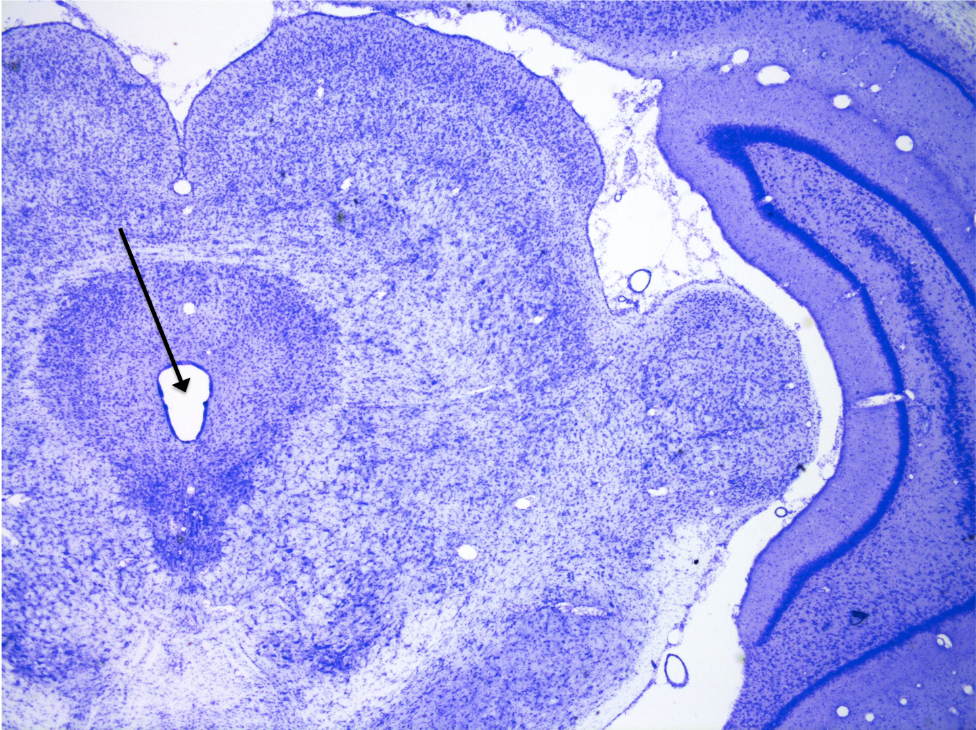

4

New cards

Optic chiasm

knowt flashcard image